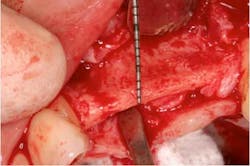

Fig. 11